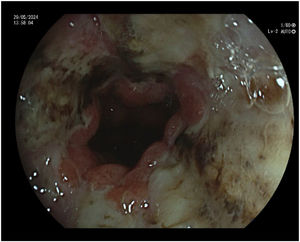

Durante el ingreso se pauta como tratamiento de soporte pantoprazol 40 mg una vez al día, metoclopramida 10 mg cada 8 horas, ondansetrón 4 mg cada 8 horas, dexametasona 4 mg una vez al día y sueroterapia. Se realiza analítica, tomografía axial computarizada (TAC) craneal, que descarta enfermedad metastásica cerebral, y TAC de tórax, abdomen y pelvis que descartan progresión tumoral. Se realiza también una esofagogastroduodenoscopia que muestra una mucosa esofágica cubierta por fibrina, con áreas necróticas (fig. 1), especialmente en esófago distal, y necrosis en bulbo duodenal, todo ello compatible con NEA. Se valora por el servicio de digestivo, concluyéndose que no existen opciones terapéuticas endoscópicas ni quirúrgicas, considerándose únicamente candidata a tratamiento de soporte.